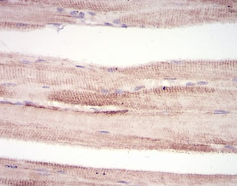

This gene encodes a member of the RING zinc finger protein family found in striated muscle and iris. The product of this gene is an E3 ubiquitin ligase that localizes to the Z-line and M-line lattices of myofibrils. This protein plays an important role in the atrophy of skeletal and cardiac muscle and is required for the degradation of myosin heavy chain proteins, myosin light chain, myosin binding protein, and for muscle-type creatine kinase.

IHC    1/200 - 1/1000